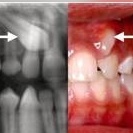

رادیوگرافی تک دندان ( پری اپیکال ) چیست؟

چرا رادیوگرافی دندان ضرورت دارد؟

رادیوگرافی دندان چیست و انواع آن